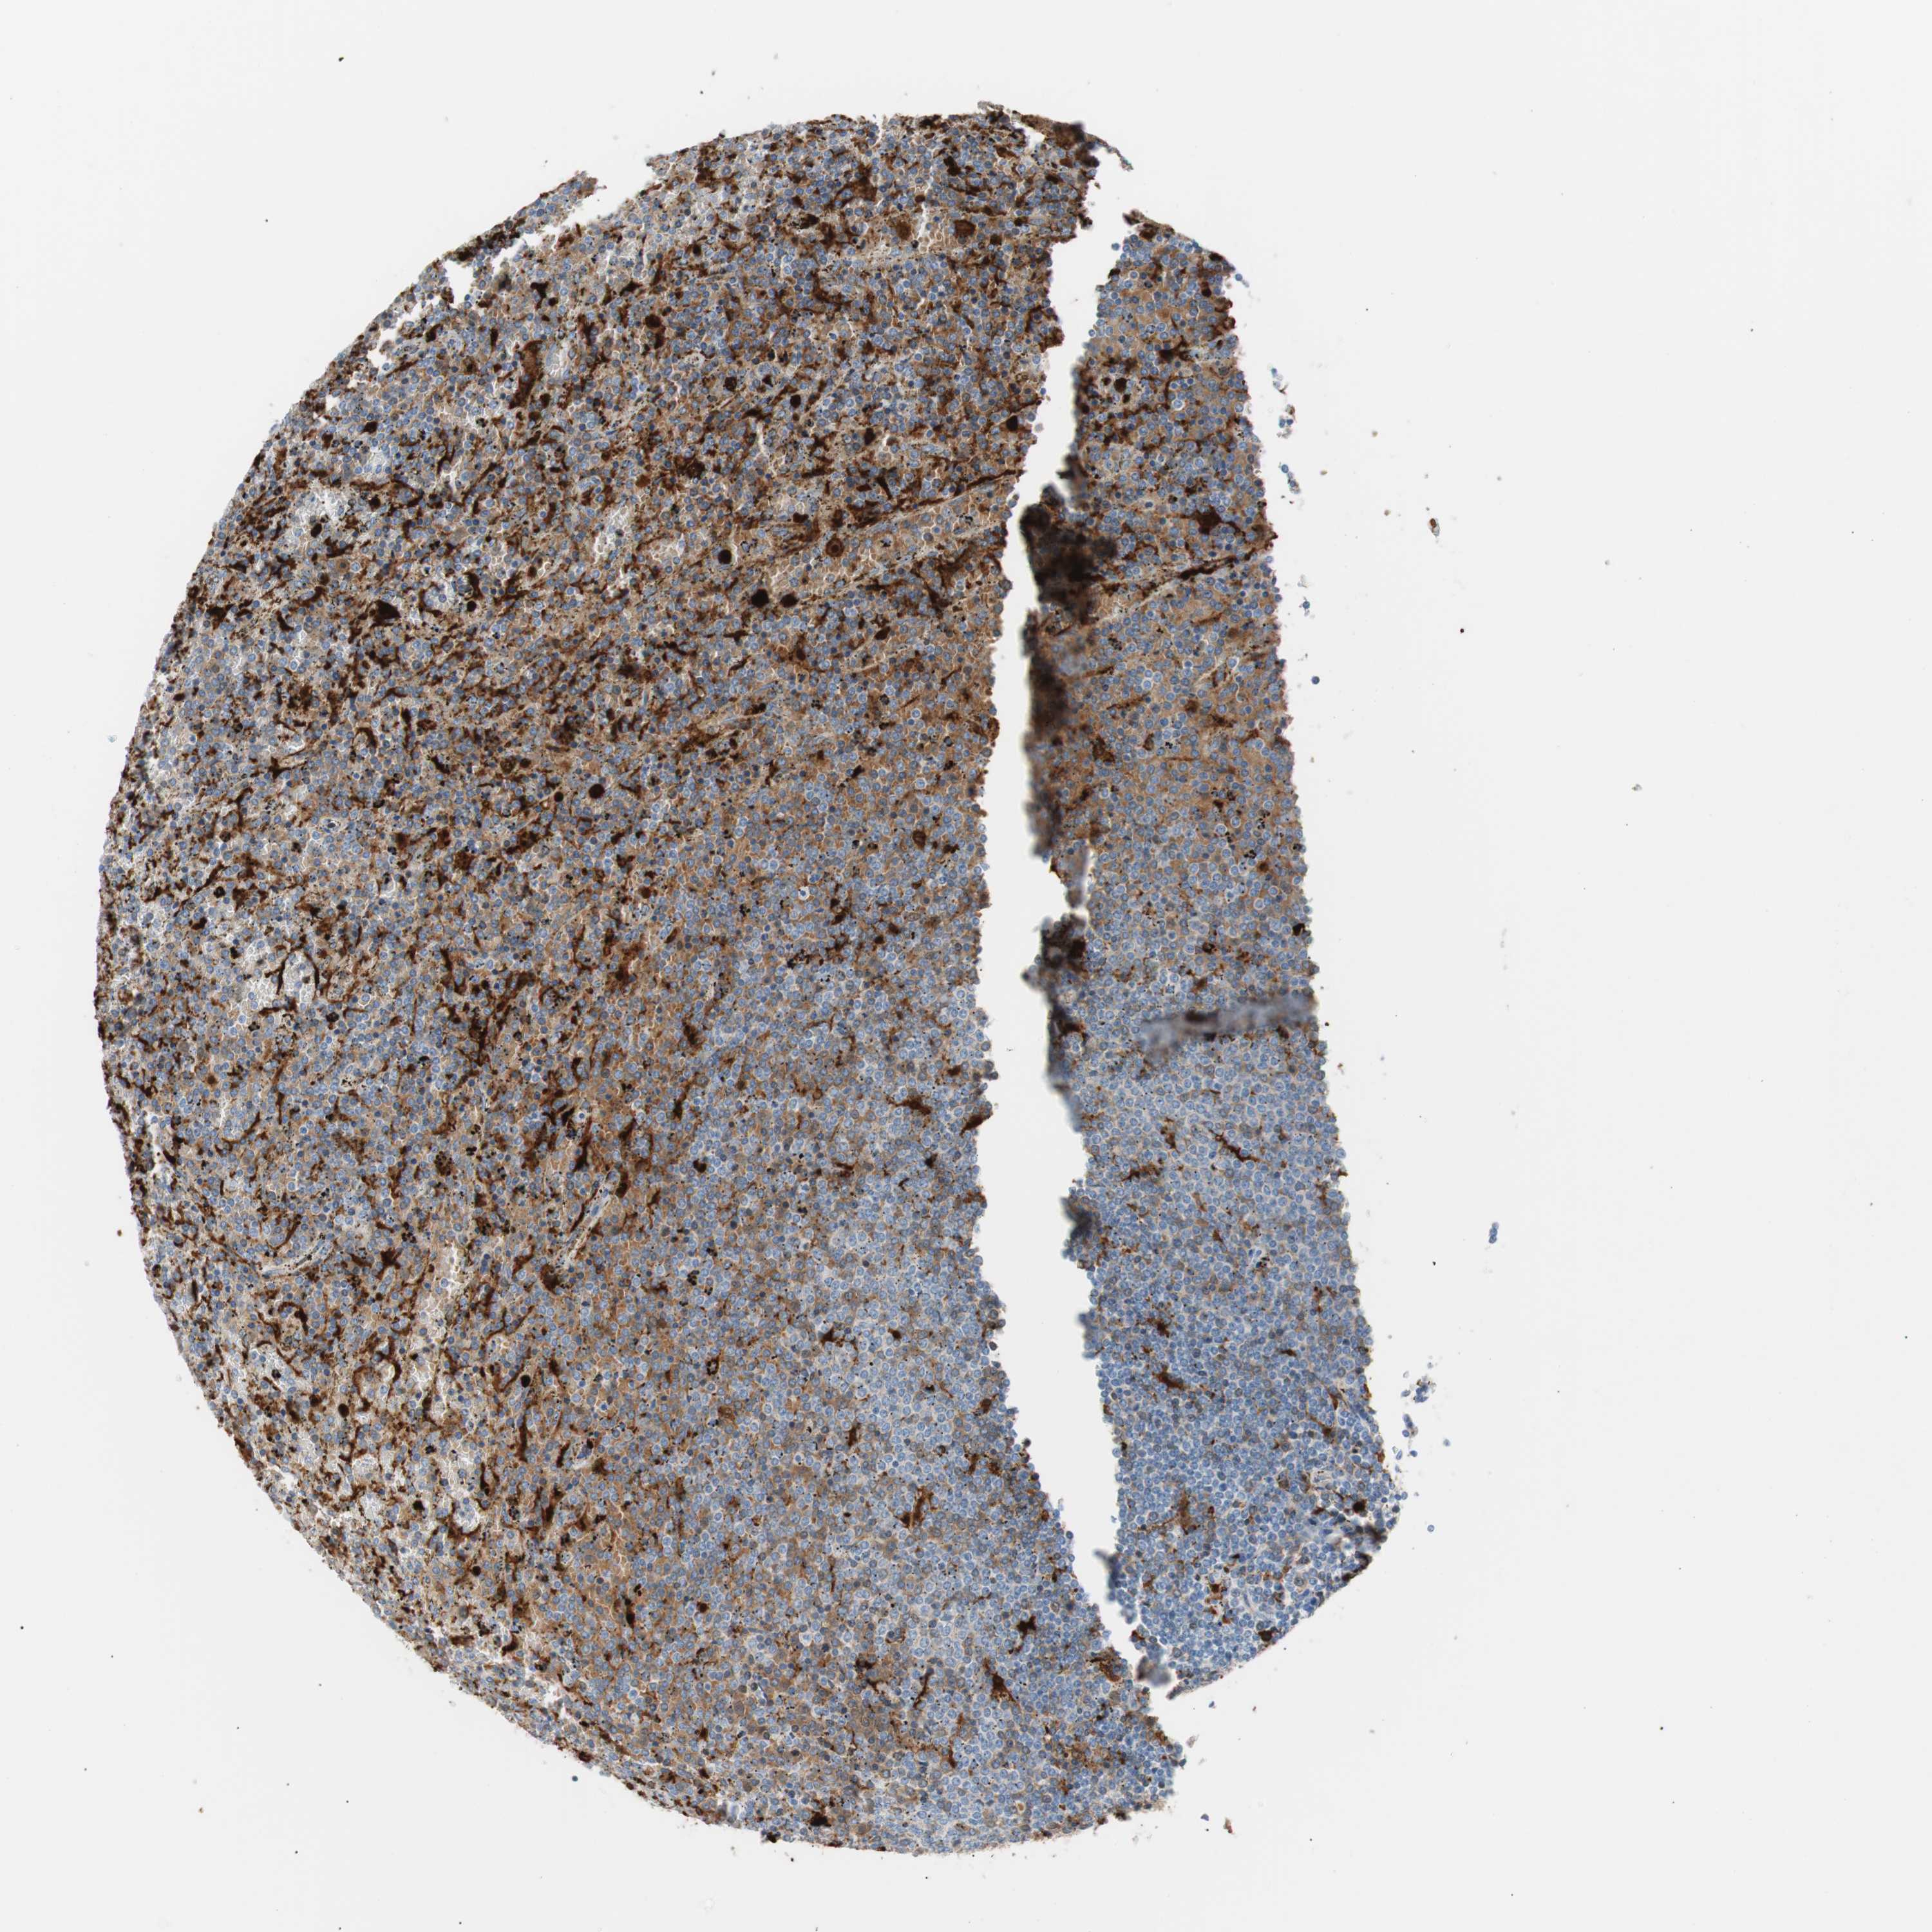

LYMPHOMA - Protein expressioni

A mouse-over function shows sample information and annotation data. Click on an image to view it in a full screen mode. Samples can be filtered based on level of antibody staining by selecting one or several of the following categories: high, medium, low and not detected. The assay and annotation is described here.

Antibody stainingi

Antibody staining in the annotated cell types in the current human tissue is reported as not detected, low, medium, or high, based on conventional immunohistochemistry profiling in selected tissues. This score is based on the combination of the staining intensity and fraction of stained cells.

Each image is clickable and will lead to virtual microscopy that enables deeper exploration of all samples and also displays staining intensity scores, fraction scores and subcellular localization as well as patient and tissue information for each sample.

Antibody HPA003980

Antibody CAB007772

Staining

High

Medium

Low

Not detected

Intensity

Strong

Moderate

Weak

Negative

Quantity

>75%

75%-25%

<25%

None

Location

Nuclear

Cytoplasmic/membranous

Cytoplasmic/membranous,nuclear

Hodgkin's disease, NOS

Malignant lymphoma, non-Hodgkin's type, High grade

Malignant lymphoma, non-Hodgkin's type, Low grade